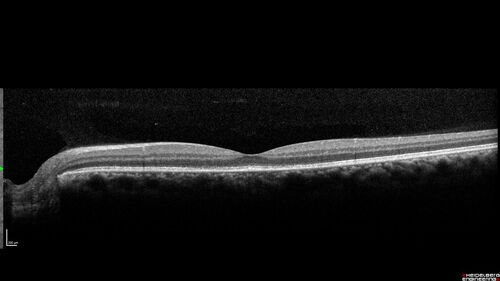

Syphilitic Chorioretinitis - 1 month post-treatment

41 year old man with vision loss for five days left eye. VA 20/32, 20/200